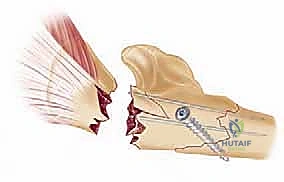

TECH FIG 3 • A. Monteggia fractures with articular involvement should be fixed distal to proximal. Fixation may require intramedullary Kirschner wires or interfragmentary fixation.

* Lag Screws: Larger fragments can be definitively fixed with antegrade lag screws inserted from the dorsal aspect of the ulna, aiming volarly into the coronoid. This requires careful trajectory planning to avoid joint penetration.

* Provisional Wires: Smaller fragments can be provisionally held with threaded K-wires and then definitively secured once the plate is applied to the dorsal aspect of the ulna, potentially capturing these fragments indirectly.

TECH FIG 3 • ( continued ) C. The olecranon fragment with attached triceps is reduced and provisionally held with medial and lateral Kirschner wires pending definitive fixation.

* Definitive Fixation: Apply a rigid plate to the dorsal cortex of the ulna, extending proximally over the olecranon. This plate will typically be a pre-contoured olecranon plate or a specifically designed Monteggia plate.

TECH FIG 3 • ( continued ) D. Final fixation for most Monteggia fractures is with a rigid plate applied to the dorsal cortex.

* Screw Insertion: Secure the plate with cortical and locking screws, ensuring optimal purchase in the olecranon and distal fragments.

TECH FIG 3 • ( continued ) D. Final fixation for most Monteggia fractures is with a rigid plate applied to the dorsal cortex.